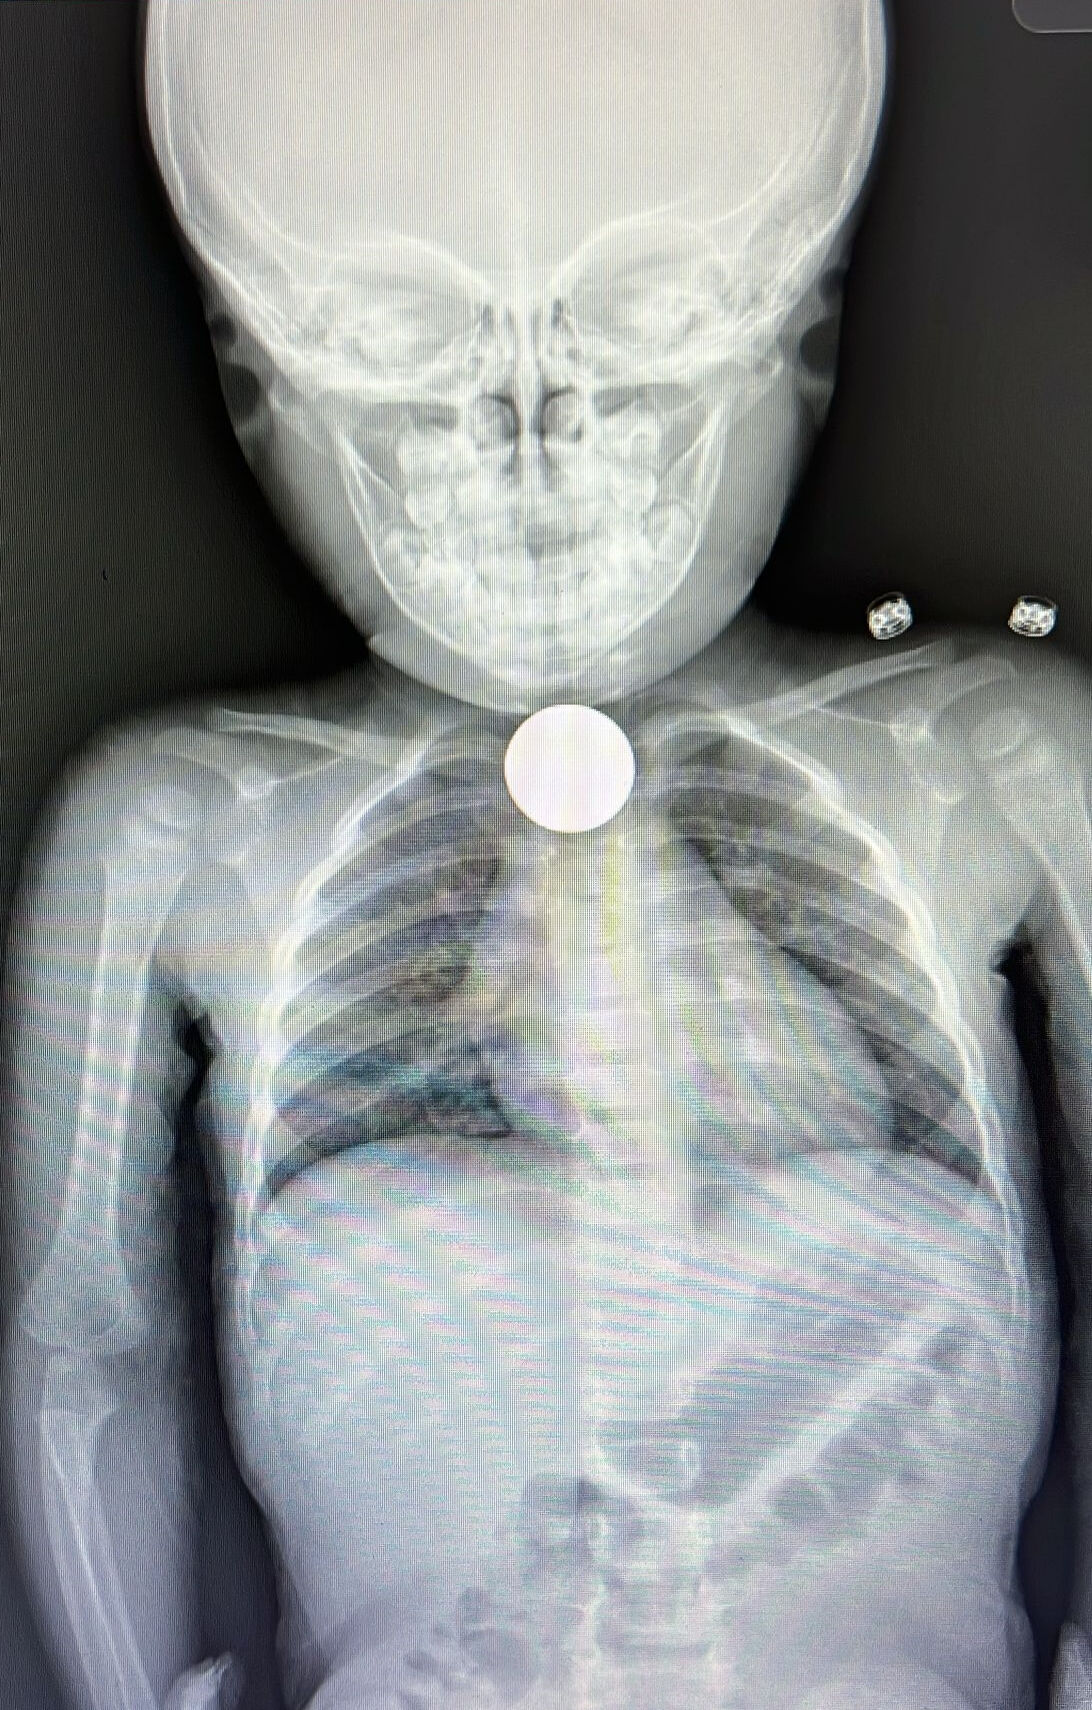

Afyonkarahisar'ın Bolvadin ilçesinde kızarma, öksürük ve nefes alamama gibi şikayetlerle hastaneye götürülen çocuğun yemek borusunda tespit edilen madeni para başarıyla alındı.

Burada yapılan detaylı tetkiklerde çocuğun yemek borusunda madeni para görüldü. Her geçen dakika durumu daha da kötüleşen İkra'nın yemek borusunu tıkayan para, başarıyla çıkarıldı. Tıbbi müdahalenin ardından çocuk yutkunmaya ve rahat nefes alıp vermeye başladı, şikayetleri sona erdi.

Nefes almakta güçlük çeken çocuğa gerekli tetkiklerin ardından müdahale kararı aldıklarını anlatan Tuncer, "Çocuk oynarken elindeki parayı yutmuş. Sonra da şikayetleri başlamış." dedi.